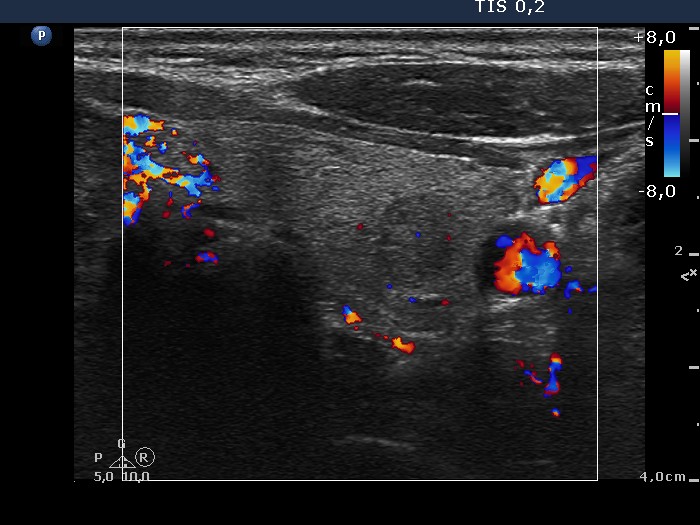

Thyroid cancers - case 670 (ultrasonographic picture 9)

Left lobe transverse scan, color Doppler mode.